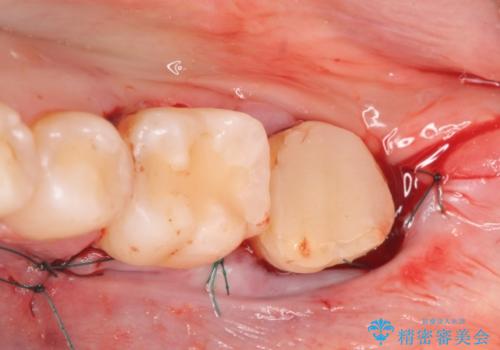

- 左下の一番奥の歯が時折激しく痛むので診て欲しいといらっしゃった方の症例です。以前に他院を受診したところ、そもそも被せ物を入れるスペースがないため抜歯しかないと言われたとのことでした。

診査の結果根尖病変を認めたため再根管治療を行った後に、被せ物を入れるスペースを作るため歯冠延長術を行いました。

歯冠延長術について

歯冠長延長術とは歯肉弁根尖側移動術とも言い、歯の高さが低くクラウン(被せ物)による治療が難しい場合に、歯茎を歯根方向に下げることで歯の高さを確保する手術です。歯の高さが十分にあることで、外れにくいしっかりとしたクラウンを被せることができます。